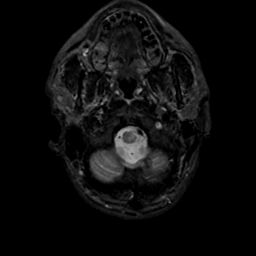

MR Study #17, July 7, 1991 -- Slice #3

[Home][Help][Clinical][Tour 1][Tour 2] Slice 3